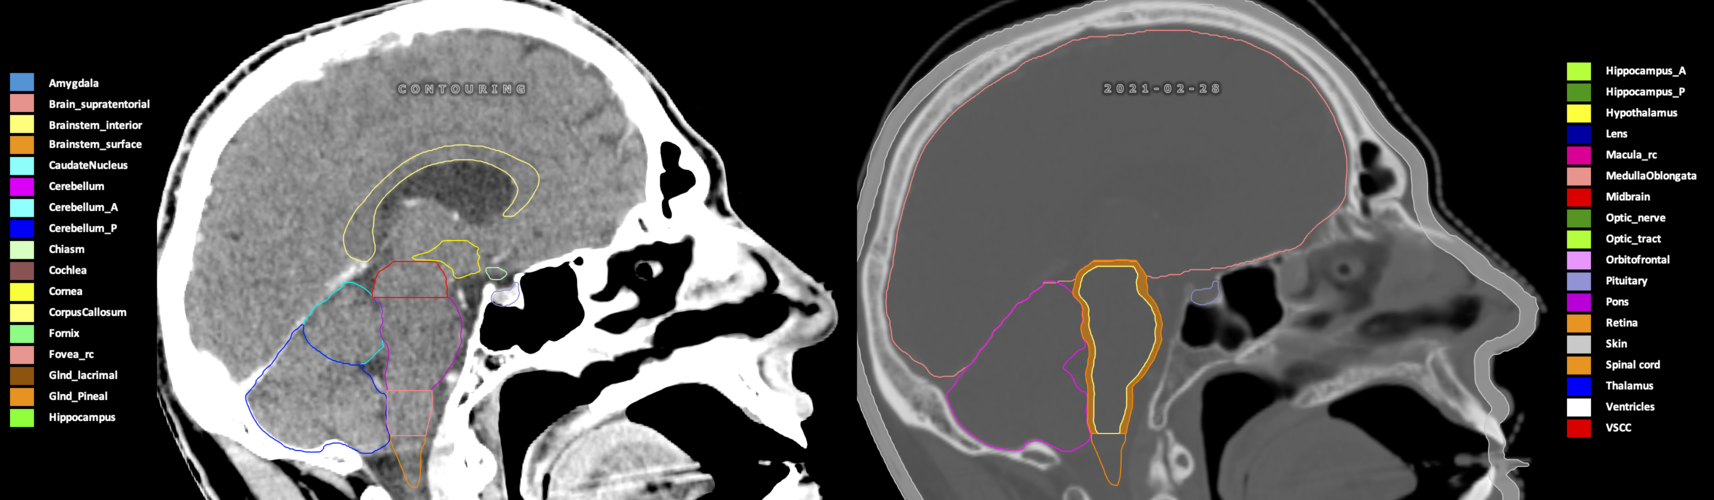

Included are all OARs known to be relevant for radiation-induced toxicity in neuro-oncology: brain, brainstem (midbrain, pons, medulla oblongata), chiasm, cerebellum (anterior & posterior), cochlea, cornea, hippocampus (anterior & posterior), hypothalamus, lens, lacrimal gland, optic nerve, pituitary, skin, and vestibular & semicircular canals. To further facilitate research on cognition, vision and radiological changes after irradiation of the brain, potential clinically-relevant OARs are included: amygdala, caudate nucleus, cerebellum (anterior & posterior), corpus callosum, fornix, macula, optic tract, orbitofrontal cortex, periventricular space (PVS), pineal gland, and thalamus.

Three-dimensional delineation of the 25 consensus OARs for neuro-oncology are shown on CT (WW/WL 120/40, 3000/600), 3T MR images, (T1Gd, T2FLAIR 1mm) and 7T MR (MP2RAGE 0.7 mm). All are presented in transversal, sagittal and coronal view.